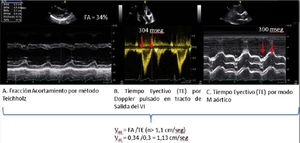

Valoración del volumen sistólico (fig. 2)Se puede realizar por medio de la integral velocidad-tiempo (IVT) y el diámetro del tracto de salida del ventrículo izquierdo (TSVI).

Estimación del volumen sistólico (VS) y del gasto cardiaco (CO) a través de la integral de velocidad (VTI) y radio (r) del tracto de salida del ventrículo izquierdo (TSVI). A) Paraesternal izquierdo ventrículo izquierdo en sístole. B) Zoom TSVI. C) Doppler pulsado TSVI 5C apical. D) Cálculos.

Un IVTTSVI<11cm se correlaciona con un índice cardiaco <2 l/min17,18.